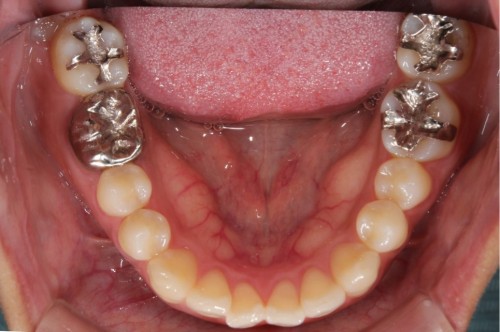

ダイレクトボンディング

費用2万円×4本

リスクとして欠ける可能性がある(修復可能)。